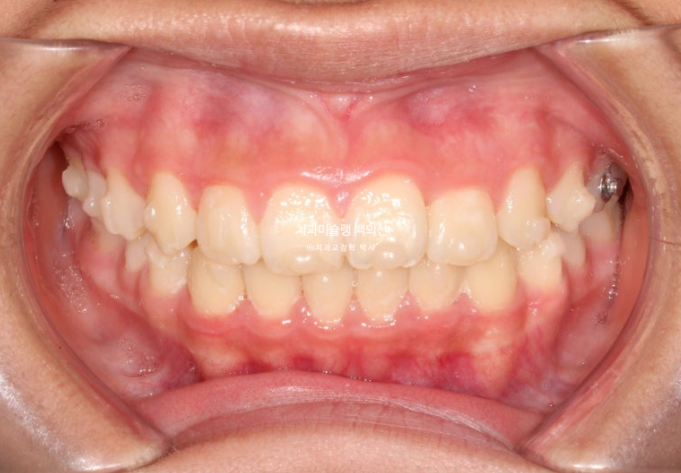

25년 5월부터 25년 7월까지 앞니 배열 개선을 위해 추가장치를 짧게 낀 후 치료를 마무리 하였습니다.

25.07

중심선은 잘 맞으며

어금니 교합은 물샐틈 없는 1급 교합관계를 보입니다.

이제 전후비교 보겠습니다.

총 치료기간은 1년 6개월이며 중간에 중심선 이슈로 잠시 쉬는 시간이 4개월 있었습니다.

재제작은 총 2회 했습니다.

24.02~25.07

치료결과가 어린이 교정이 아닌, 정식 성인교정 치료 결과에 준하는 만큼 유지장치도 철저하게 들어갑니다.

어긋난 중심선이 맞아졌으며 기울어진 앞니 치축도 좋아졌습니다.

앞니가 깊게 물리는 과개교합도 좋아졌습니다.